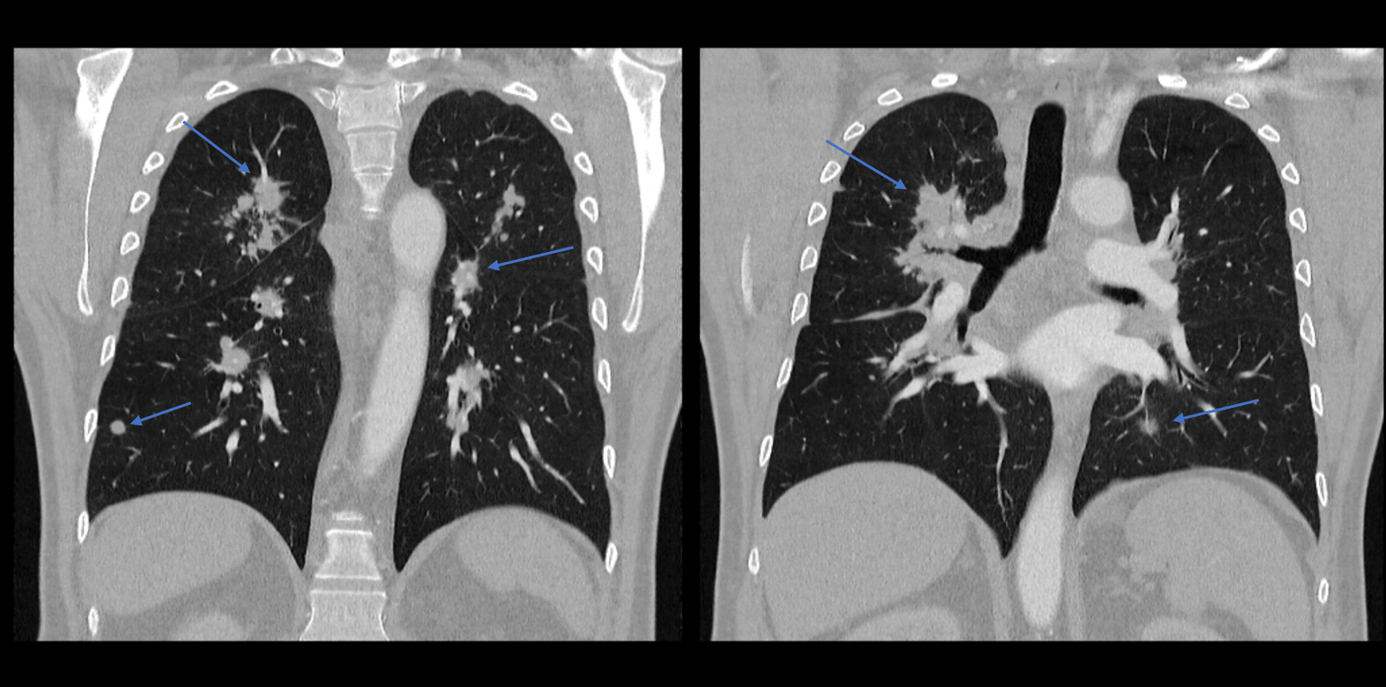

Aufgrund des pulmologischen Befundes wurde eine Computertomographie veranlasst. Im Weichteilfenster zeigten sich massiv vergrößerte mediastinale und bihiläre Lymphknoten (gelbe Pfeile). Im Lungenfenster zeigten sich multiple, zum Teil scharf abgrenzbare, Rundherde, zum Teil grobfleckige Infiltrate (blaue Pfeile).